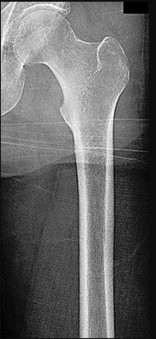

A 13-year-old overweight male presents with an acute exacerbation of chronic right groin and knee pain. He walks with an externally rotated gait. Radiographs confirm a severe Slipped Capital Femoral Epiphysis (SCFE). Pathophysiologically, the slippage in SCFE occurs primarily through which specific histological zone of the proximal femoral physis?

Options:

Correct Answer: Zone of hypertrophy

Explanation:

Slipped Capital Femoral Epiphysis (SCFE) typically occurs due to mechanical shear forces across a weakened physis during the adolescent growth spurt. Histologically and biomechanically, the weakest layer of the growth plate is the zone of hypertrophy. The slippage classically occurs through this layer because the chondrocytes are enlarged, and the extracellular matrix is sparse compared to the reserve or proliferative zones, making it highly susceptible to shear stress.